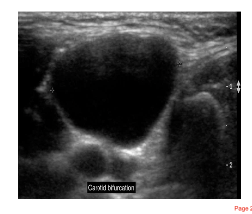

Ultrasound characteristics of a true cyst in neck and

associated structures sonography

• Anechoic (isoechoic)

• Posterior enhancement

• Posterior wall definition

• Side wall definition

• No internal echoes

Neck ultrasound: common cystic locations and other

regions of patholog

Thyroglossal duct cysts- most commn

• Brachial cleft cyst

• Miscellaneous cystic masses and

Other common pathology regions:

• non-cystic masses

• Lymphatic nodes

• Salivary glands